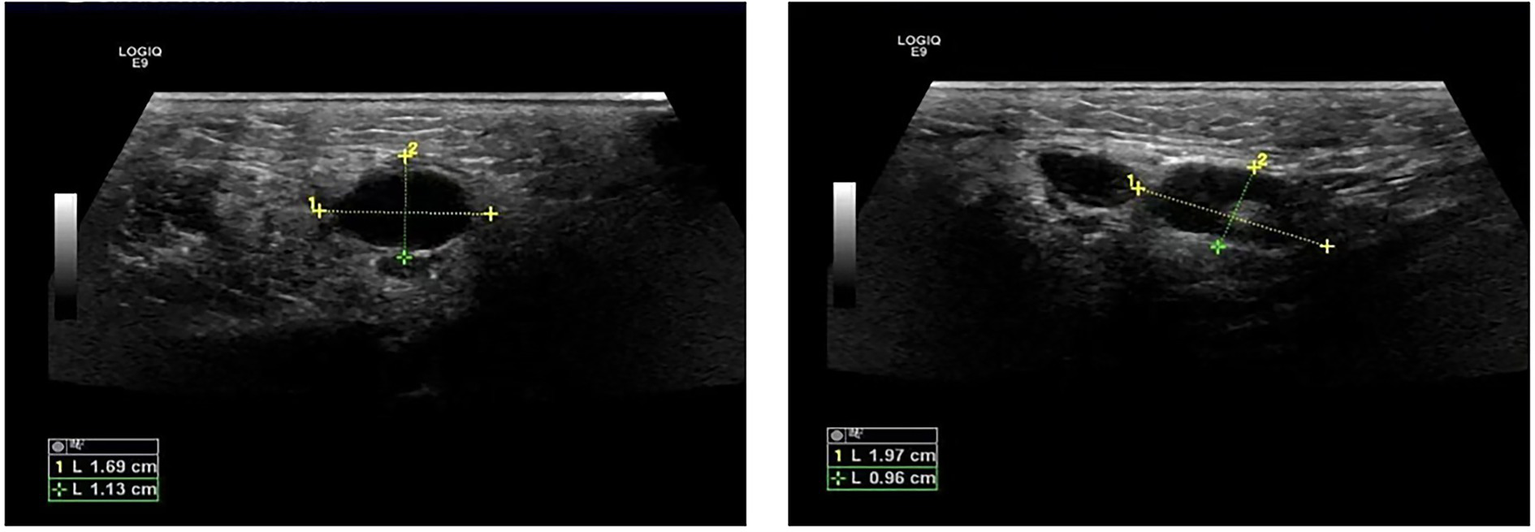

The patient was a 47-year-old female with a right maxillofacial abscess accompanied by distension and pain for 14 days. On November 22, 2024, the patient visited the local hospital’s Department of stomatology and was initially diagnosed with submandibular space infection. After local puncture and pus drainage, intravenous infusion of drugs such as clindamycin hydrochloride, levofloxacin and metronidazole for 3 days, the local symptoms worsened. On November 25, 2024, the patient visited the Oral and maxillofacial surgery outpatient Department of our hospital. The blood routine test did not show a positive result. The ultrasound examination indicated that a hypoechoic mass could be seen in the superficial part of the right masseter muscle of the patient, approximately 1.7*1.1 cm in size, with a clear boundary, regular shape, and uniform internal echo. No obvious blood flow signal was observed within it. Multiple lymph nod-like echoes could be seen in the right submandibular gland area, approximately 2.0*1.0 cm in size, with a clear structure and no obvious blood flow signal. Specialized physical examination indicated that the swelling range in the right submandibular area was approximately 2.0*1.5 cm (as shown in Figure 1), with local skin redness and swelling, elevated local skin temperature, tenderness (+), local fluctuation sensation, and slightly limited occlusal function. The re-diagnosis was submandibular space infection. Intravenous infusion of clindamycin, levofloxacin, ornidazole and other drugs for 3 days, but the therapeutic effect was not good. On November 29, 2024, the patient was referred to the Department of Infectious Diseases of our hospital. Based on her long-term epidemiological history of contact (including feeding and delivering) with livestock such as cattle and sheep, brucellosis is highly suspected. The suspension was sent to Jilin Jinyu Medical Laboratory for sequencing of the next generation of the metagenome (mNGS) the results showed that the relative abundance of Brucella with sequence number of 9133191 was 99.97%, and the coverage of Brucella suis with sequence number of 8525228 was 98.94%. Supplementary Brucella test tube agglutination method test suggests Brucella test tube agglutination 1:200++++. The blood culture and drug sensitivity tests were completed, indicating that the pathogenic bacterium was Brucella. Combined with the epidemiological history, metagenomic next-generation sequencing (mNGS) (as shown in Figure 2) and other auxiliary examination results, the diagnosis was modified to brucellosis. Surgical dressing changes were performed daily, and intravenous infusion of doxycycline 0.1 g q12h and rifamycin 0.5 g q12h was carried out. After 6 days of anti-brucellosis treatment, the patient’s symptoms were relieved and the patient was discharged. Blood cultures were negative at the first, third and sixth month after discharge (see Table 1).

Figure 1

Ultrasound images of abscess.